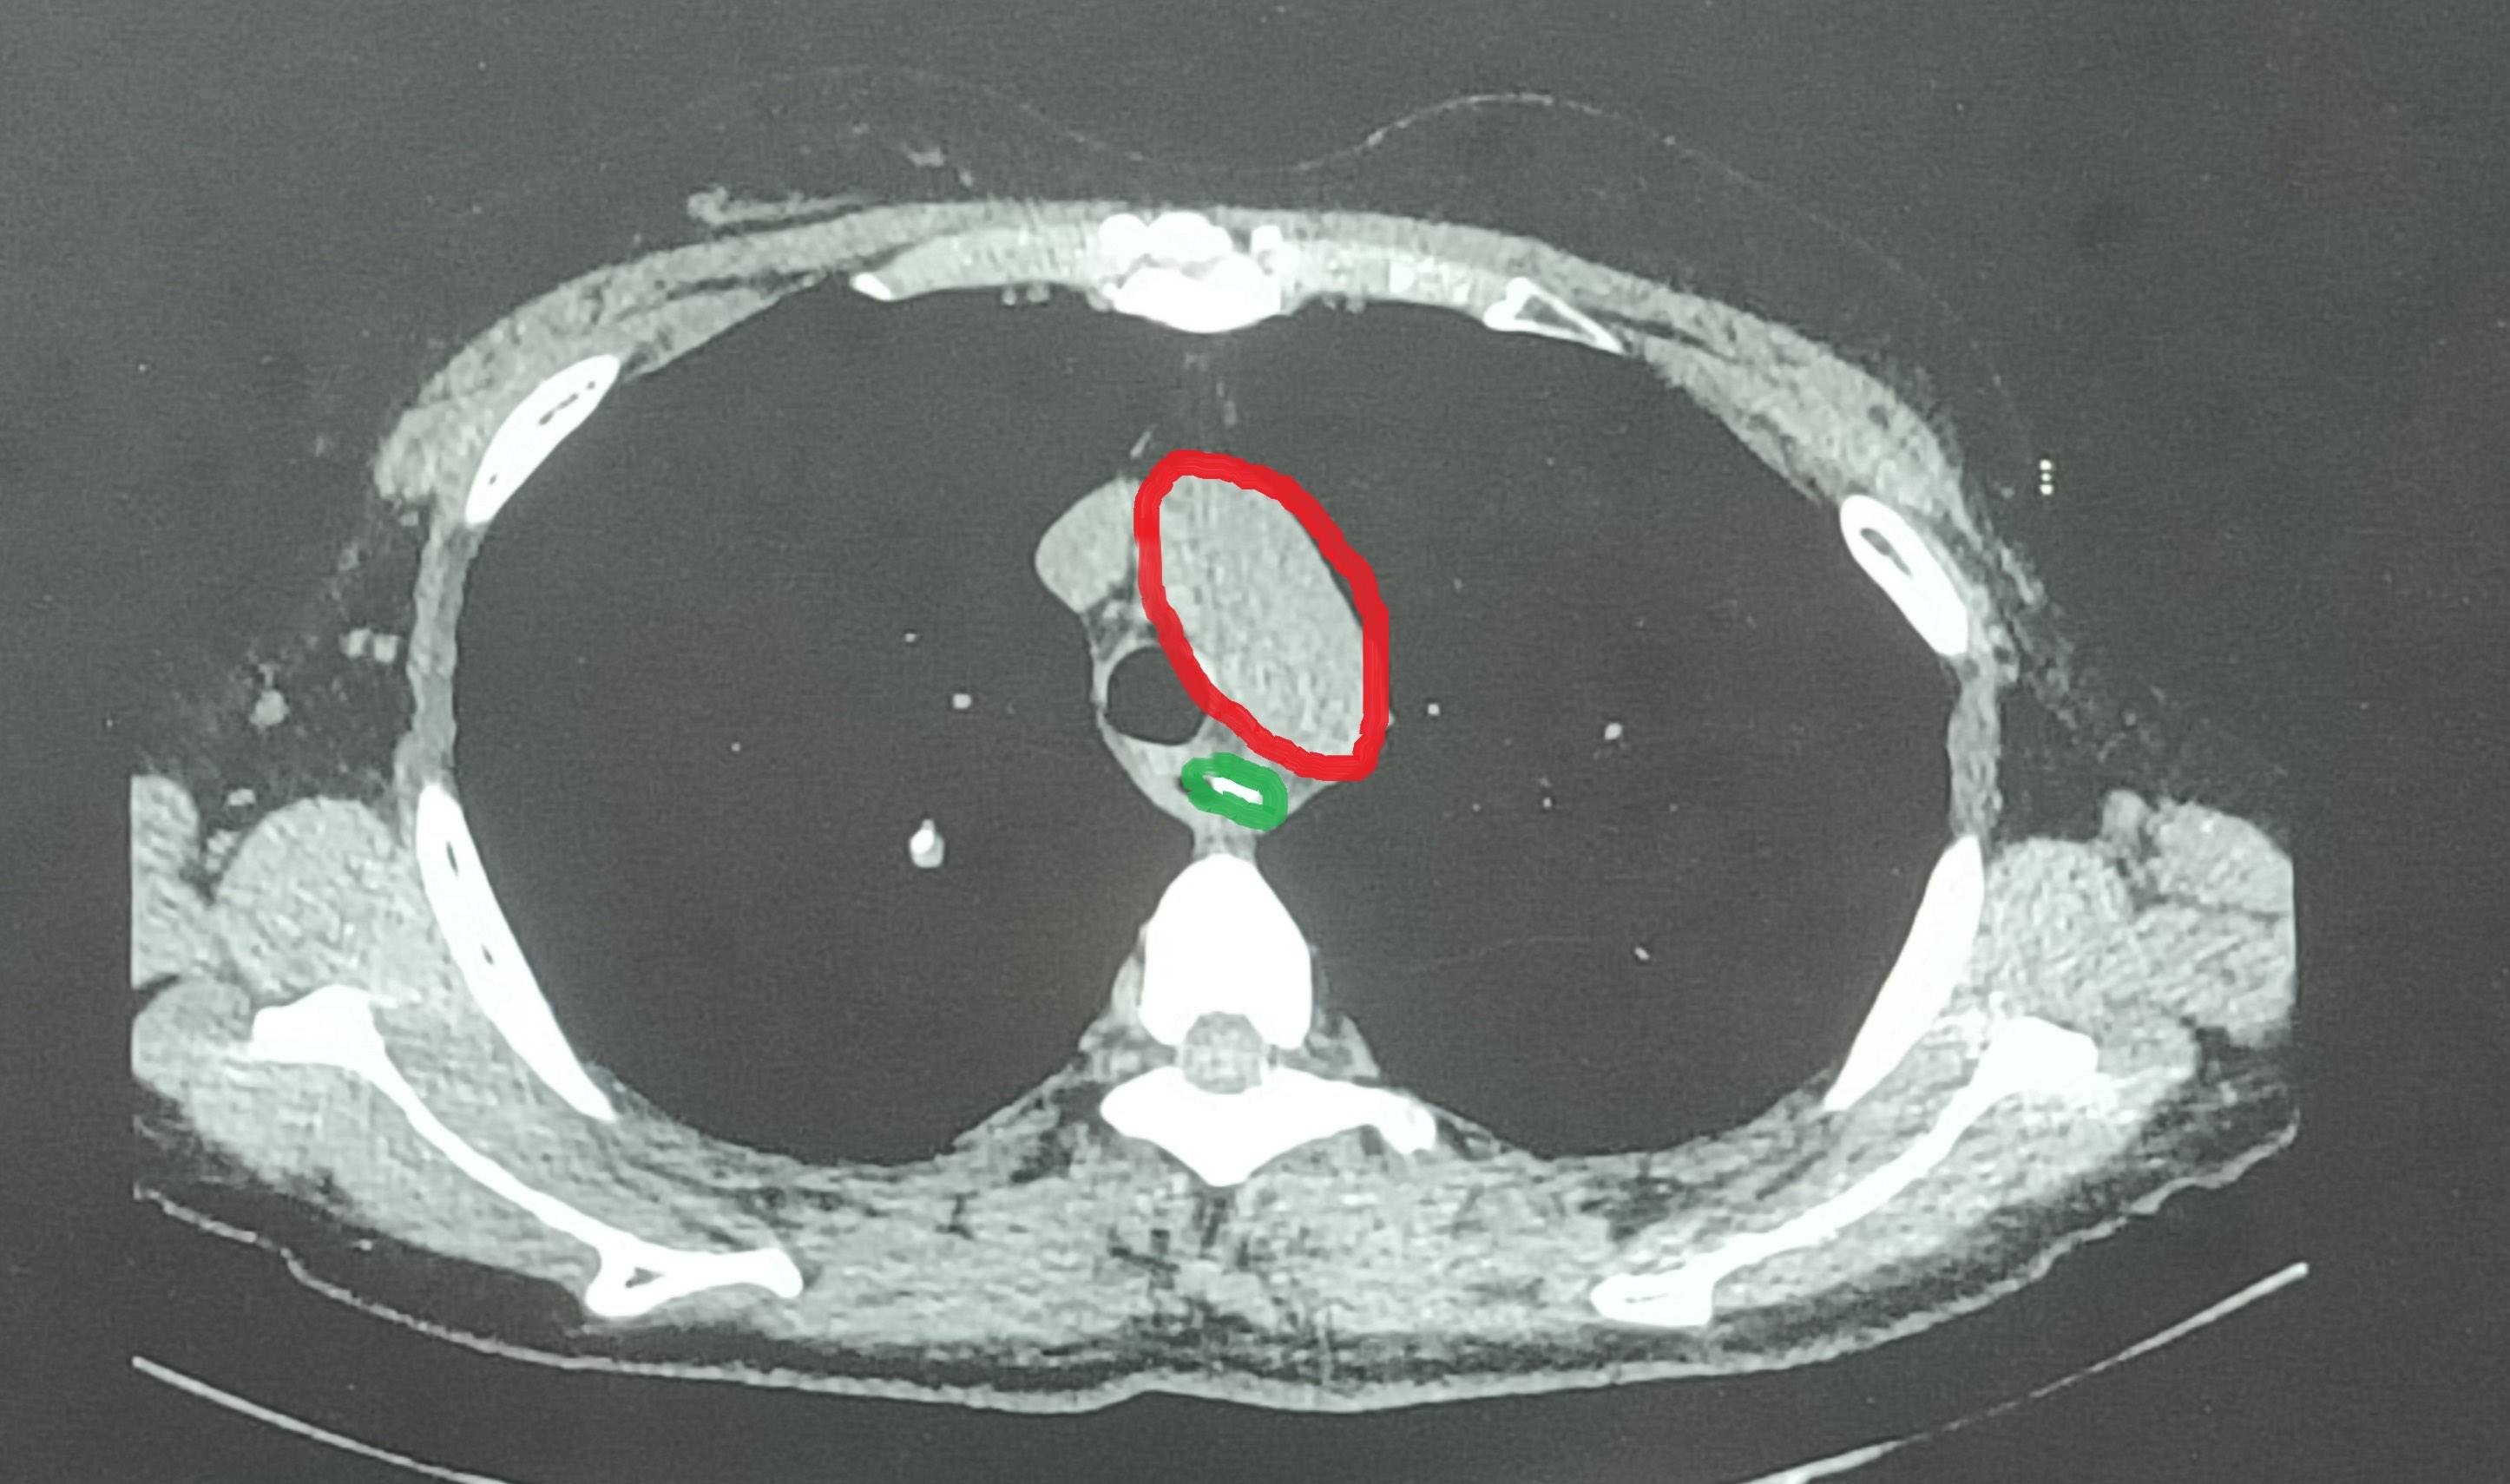

ct提示食管异物并纵膈脓肿形成

图片尺寸1920x1080